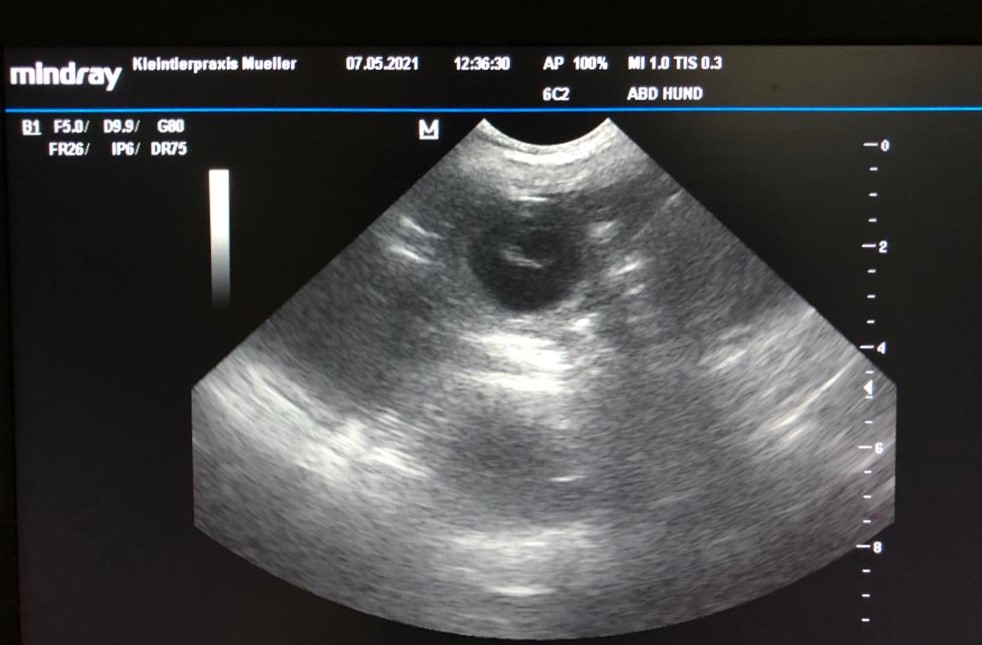

Tag 26. Nun ist es sicher, die Aufnahmen der Ultraschalluntersuchung vom 07.05.2021 sind eindeutig. Bashira ist trächtig, hurra wir freuen uns riesig und hoffen nun, dass alles gut verläuft. Wir erwarten unsere kleinen Fellnasen um den 13.06.2021.